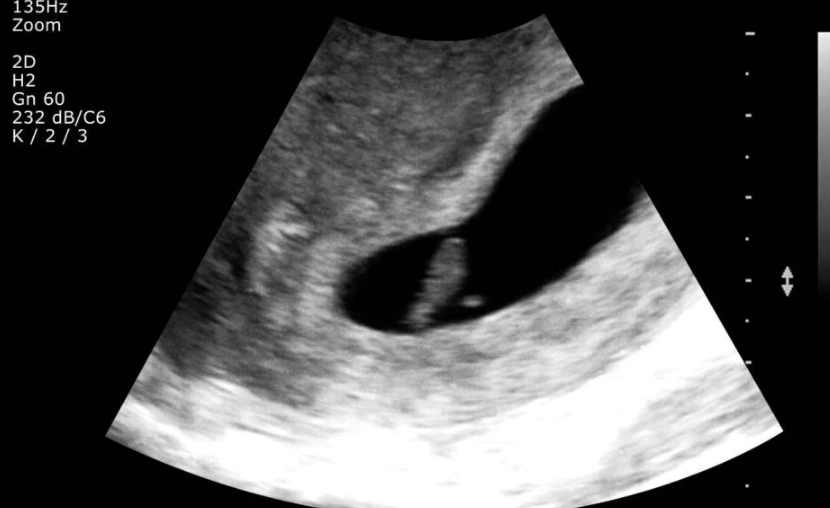

So, an ultrasound this early is often a transvaginal one (where a probe is inserted into the vagina). It gets a closer, clearer view than an abdominal scan. Here's the breakdown of what a sonographer or doctor is typically looking for at this stage:

| Gestational Sac | Maybe, just barely. | This is the first structure to become visible. It's a small, fluid-filled sac that surrounds the embryo. It might be seen as a tiny black dot in the uterus. If it's not seen, it could simply be too early. |

| Location of Pregnancy | Yes, this is key. | The most critical job of an early scan is to confirm the pregnancy is inside the uterus (intrauterine). This rules out an ectopic pregnancy, which is a serious medical condition. |

This is incredibly common at 4-5 weeks. The report might say something like "gestational sac visualized, fetal pole not yet identified." This doesn't automatically mean something is wrong. It often just means it's too early. Your doctor will likely recommend a follow-up ultrasound in 1-2 weeks. During that time, the embryo should grow enough to become visible. The wait is tough, but it's a standard part of early pregnancy management.

The "Everything Looks On Track" Scenario

If they see a gestational sac in the uterus that measures appropriately for your dates, that's a great first sign. It confirms an intrauterine pregnancy, which is a major relief. They'll give you an estimated due date based on the sac size and schedule your next prenatal appointment or scan for a few weeks later.